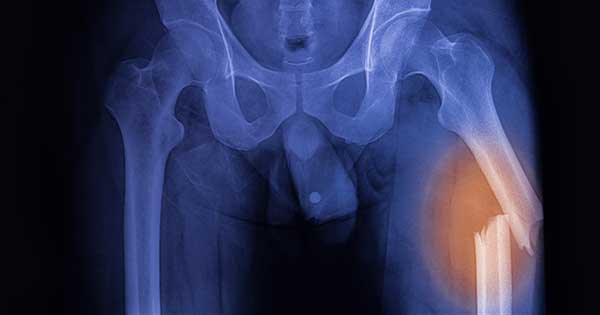

Una fractura de fémur es una lesión grave que consiste en una rotura o grieta en el fémur, el hueso más largo y fuerte del cuerpo humano. Este hueso conecta la cadera con la rodilla y es fundamental para la movilidad.

• Fractura de la diáfisis femoral: Afecta la parte central del fémur y es más común en adultos jóvenes.

• Fijación interna: Se utilizan placas, tornillos o clavos para unir los fragmentos óseos.